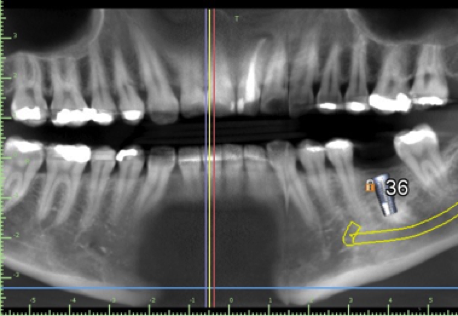

1. CBCT and model merge

Supply a CBCT of the patient and a PVS impression or intra oral scan. We will accurately merge the model with the CBCT so the guide can be made to fit accurately and be tooth and if need be tissue supported. This is a special feature that allows us to offer perfectly fitting guides. Edentulous solutions are also available including tissue or bone supported guides.

2. Virtual implant placement

Supply us with the implant brand and size and we will position it exactly to your specifications and in relation to the virtual final tooth position. We will send a written report for you to check and note any changes if needed. We will not make the guide until you are 100% satisfied with the virtual placement. Alternatively use free software to plan the case yourself and send us the plan file and we can make the guide from that.